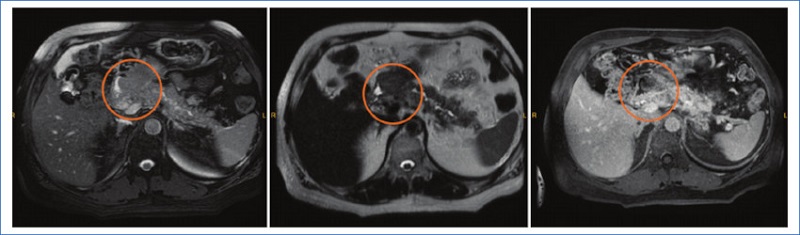

Se presenta el caso de un paciente de 62 años, con antecedente de alergia al contraste iodado, que consulta por ascenso paulatino de su antígeno prostático específico (PSA), presentando en el analítico sanguíneo un valor de 10,70 ng/ml. Se realizó una resonancia magnética (RM) multiparamétrica, la cual mostró una lesión PIRADS 4 de 15 mm localizada en el ápex derecho de la próstata en la región fibromuscular anterior. Se solicitó una biopsia de próstata que informó adenocarcinoma de próstata score de Gleason 6. Se estadificó enfermedad prostática con 18F-PET-PSMA-1007, cuyo informe reveló captación heterogénea del radio trazador con un SUVmáx de 4 en la región anterior de la próstata. Además, se observó una lesión en la porción cefálica de la glándula pancreática la cual mostró una moderada captación del trazador con un SUVmáx de 4,5 acompañada de dilatación del conducto pancreático principal (Fig. 1). Dado su antecedente de alergia al contraste iodado, se solicitó una RM de abdomen, donde se visualizó una formación en el páncreas, isointensa en secuencias ponderadas en T2 e hipoisointensa en secuencias ponderadas en T1, la cual se localizaba en la cabeza generando una compresión del conducto pancreático común (Fig. 2). Además, se constató elevación del marcador tumoral Ca 19.9, por lo cual se solicitó biopsia guiada por ecografía endoscópica, la cual informó la presencia de un adenocarcinoma moderadamente diferenciado de páncreas. Actualmente el paciente se encuentra en vigilancia activa por su adenocarcinoma de próstata y realizando quimioterapia neoadyuvante para una eventual duodenopancreatectomía.

La RM, por otro lado, facilita la detección de tumores en una fase más temprana, proporcionando un análisis exhaustivo de los cambios morfológicos en el parénquima del páncreas y el conducto pancreático. Además, la RM es valiosa en pacientes con insuficiencia renal o sensibilidad al contraste yodado en el diagnóstico de formaciones pancreáticas8.